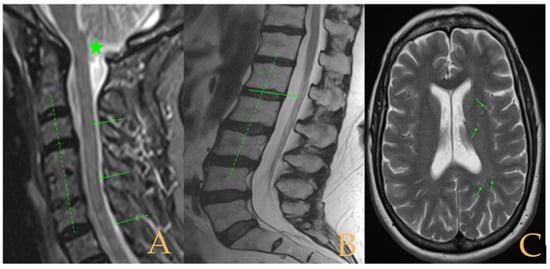

The MRI showed (Figure 8): descent of the cerebellar tonsils and increase of the supracerebellar space, straightening of the cervical spine, multiple protrusions, and discrete central spinal cord oedema C5-C7, mild scoliosis in the thoracic spine, and somewhat tense aspect of the spinal cord. The conus medullaris was at the level of the lower third of the L2 vertebra. Disc disease L5-S1. Tarlov cyst at S2. On the full-spine X-rays, there was dysmetria of the lower extremities with shortening of the left lower extremity estimated to be 1 mm at the level of the acetabular roofs and 6 mm at the level of the iliac crests. Levoconvex lumbar scoliosis was estimated at 5°, and levoconvex cervicothoracic scoliosis was estimated at 3° (both total, including all vertebrae). The estimated lateral curvatures, including all vertebral bodies in each region, were cervical lordosis 4°, thoracic kyphosis 32°, and lumbar lordosis 40°.

Figure 8. Imaging of patient 8. A: MRI of the posterior fossa with descent of the cerebellar tonsils (arrow) below McRae line (green line); B: cervical MRI with straightening of the cervical spine (interrupted line) and C5-6-7 disc disease (stars); and C: conus medullaris at the level of the lower third of L2 (arrow) and L5S1 disc disease (star).